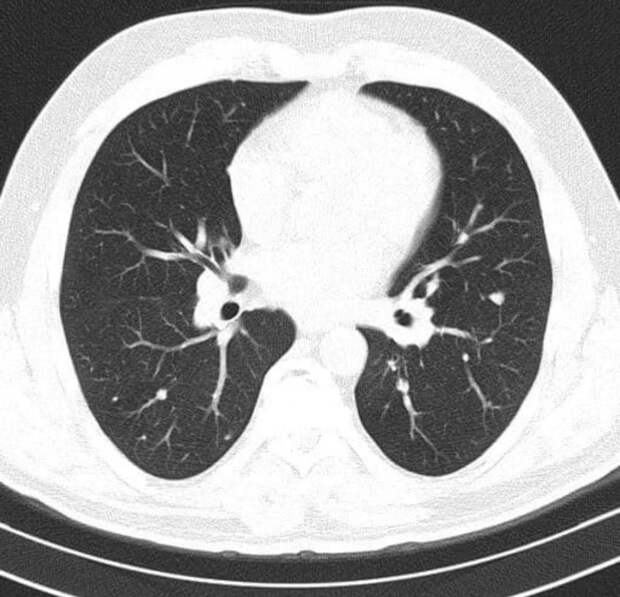

КТ грудной клетки - ключевой методом при идентификации осложнений: бронхопневмонии, вызванной вирусной инфекцией.Компьютерная томография значительно информативнее обычной рентгенографии. Вместо одного изображения во фронтальной проекции, КТ выполняет множество поперечных срезов, формируя детализированные изображения тканей, микроскопические детали повреждений. Томография позволяет врачам видеть легкие и другие структуры дыхательной системы, включая артерии, вены, бронхи и трахеи.

Компьютерная томография особенно ценна при диагностике воспалительных процессов, таких как пневмония. Она позволяет точно определить зону поражения, установить этиологию заболевания и идентифицировать инфекционные агенты. Эти сведения критически важны для постановки диагноза, планирования лечения.